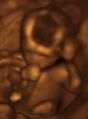

![]() Obstetric sonogram of a fetus at 16 weeks. The bright white circle center-right is the head, which faces to the left. Features include the forehead at 10 o'clock, the left ear toward the center at 7 o'clock and the right hand covering the eyes at 9:00. | |

Modern 3D ultrasound images provide greater detail for prenatal diagnosis than the older 2D ultrasound technology.[6] While 3D is popular with parents desiring a prenatal photograph as a keepsake,[7] both 2D and 3D are discouraged by the FDA for non-medical use,[8] but there are no definitive studies linking ultrasound to any adverse medical effects.[9] The following 3D ultrasound images were taken at different stages of pregnancy:

Fetus at 20 weeks